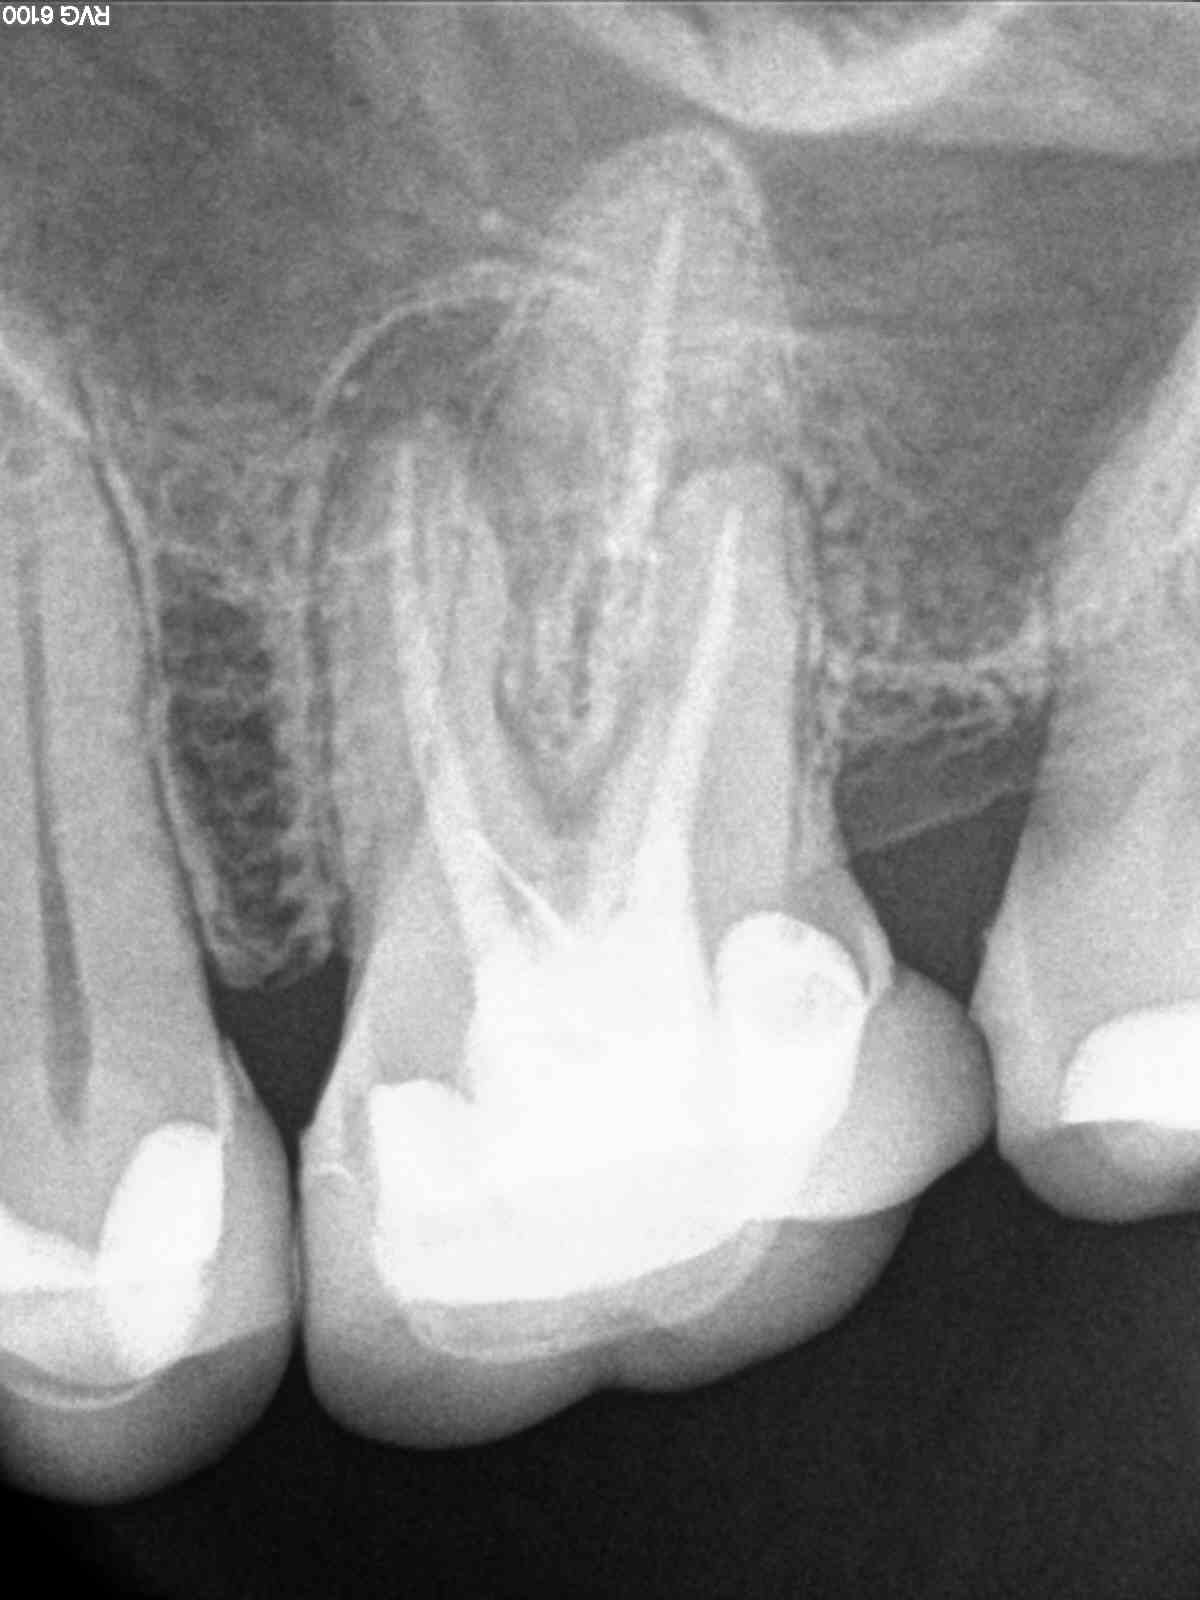

R1

1200 × 1600

X-Bein